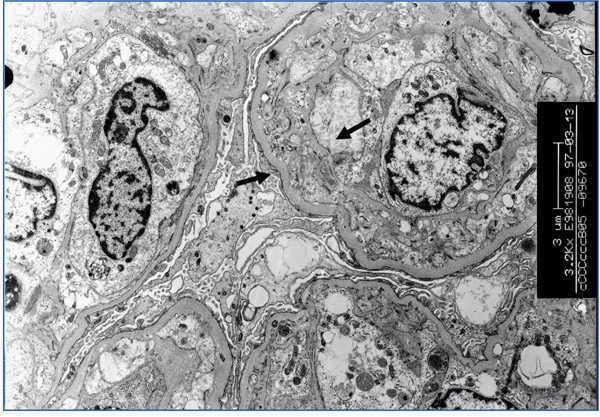

TG was defined by Maryniak in 198549 as a heterogeneous glomerular disease consisting of double contours in the glomerular capillary walls (Figure 4) with special ultrastructural features, including electron-lucid subendothelial areas, glomerular basement membrane multilamination and mesangiolysis (Figure 5). An electron microscope must be used to diagnose it and the systematic use of this microscopy could enable TG to be diagnosed in very early stages. Studies carried out on protocol biopsies have shown that there are ultrastructural changes in TG in biopsies taken one month after the transplantation.15,56 The fact that it hides its aetiopathogenesis for some time, its similarity in the optical study and the electron microscope with thrombotic microangiopathy (TMA) led to demonstrating that the endothelial cell is the ‘target’ in both conditions. The endothelial cell would be the direct point of attack of the circulating anti-donor antibodies in TG. In both conditions, similar changes occur in the optical microscope as well as at the ultrastructural level, where they share comparable disorders, such as oedema or the subendothelial ‘rarefaction’ of the glomerular basement membrane, formation of double contours and even, ‘mesangiolysis’. There is increasing proof that TMA and TG are similar means of expression of the glomerulus in an endothelial lesion, although they have different clinical presentations, as there is no haemolytic-uraemic syndrome evidence in TG.50 In our experience, after reviewing 1110 biopsies of kidney transplantations, TG is the most common glomerulopathy with 42 cases. This represents 36.8% of glomerular diseases in the allograft and 3.7% of all allograft pathologies. It is important to highlight the poor prognosis of this condition, as 97% of cases lost the allograft in our experience.

Figure 4. Transplant glomerulopathy

Figure 5. Transplant glomerulopathy